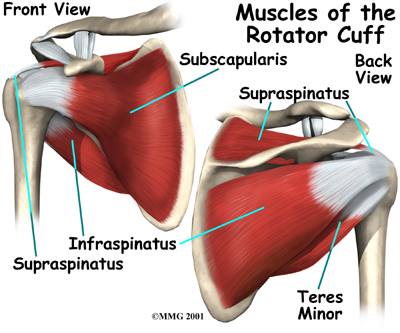

The rotator cuffconnects the humerus to the scapula.

The is actually made up of the tendons of four muscles: the supraspinatus, infraspinatus, teres minor, and subscapularis.

The is actually made up of the tendons of four muscles: the supraspinatus, infraspinatus, teres minor, and subscapularis.

Tendons attach muscles to bones. Muscles move bones by pulling on tendons. The muscles of the rotator cuff also keep the humerus tightly in the socket. A part of the scapula, called the glenoid, makes up the socket of the shoulder. The glenoid is very shallow and flat. A rim of soft tissue, called the labrum, surrounds the edge of the glenoid, making the socket more like a cup. The labrum turns the flat surface of the glenoid into a deeper socket that molds to fit the head of the humerus.

Even nonsurgical treatment for shoulder instability usually requires a rehabilitation program. The goal of physical therapy is to strengthen the rotator cuff and shoulder blade muscles to make the shoulder more stable.

Your physical therapist may employ heat or ice treatments to ease pain and inflammation. We use hands-on treatments and various types of exercises to improve the range of motion in your shoulder and nearby joints and muscles. Later, you will do strengthening exercises to improve the strength and control of the rotator cuff and shoulder blade muscles. Our physical therapist will help you retrain these muscles to keep the ball of the humerus in the socket. This will improve the stability of the shoulder and help your shoulder joint move smoothly.

At about six weeks, we will have you start doing more active strengthening. These exercises focus on improving the strength and control of the rotator cuff muscles and the muscles around the shoulder blade. Our physical therapist will help you retrain these muscles to keep the ball of the humerus in the socket. This helps your shoulder move smoothly during all your activities.

By about the tenth week, we will start have you begin more active strengthening. These exercises focus on improving strength and control of the rotator cuff muscles. Strong rotator cuff muscles help hold the ball of the humerus tightly in the glenoid to improve shoulder stability.